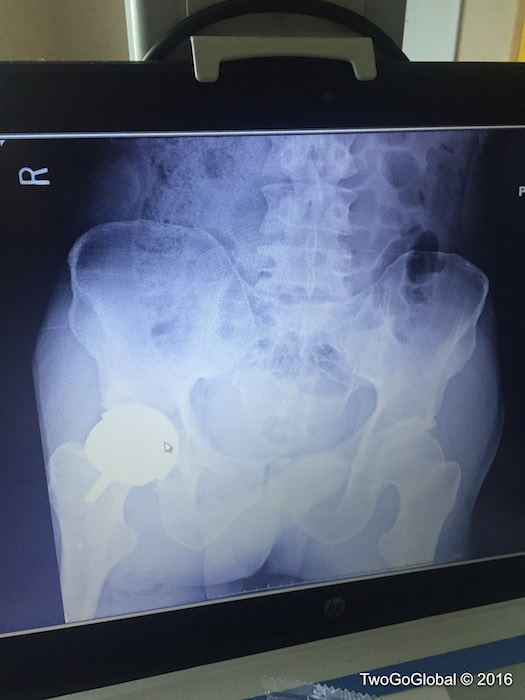

Relaxed before going under yet another surgeons knife Aug 27, 2016Relaxed before going under yet another surgeons knife